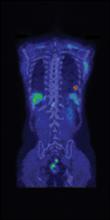

Siemens Healthcare has introduced Biograph mCT Flow, a positron emission tomography/computed tomography (PET/CT) system that, for the first time ever, overcomes the limitations of conventional bed-based PET/CT with FlowMotion, a revolutionary new technology that moves the patient smoothly through the system’s gantry, while continuously acquiring PET data. Biograph mCT Flow with FlowMotion takes routine image quality to a new level by enabling imaging protocols based on the organ’s need.